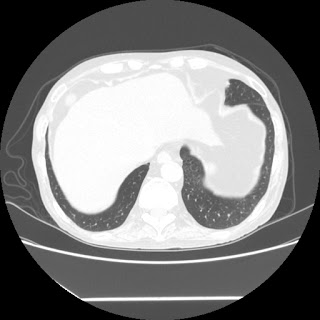

A 58 years old man with....

HRCT done on 17Mar16